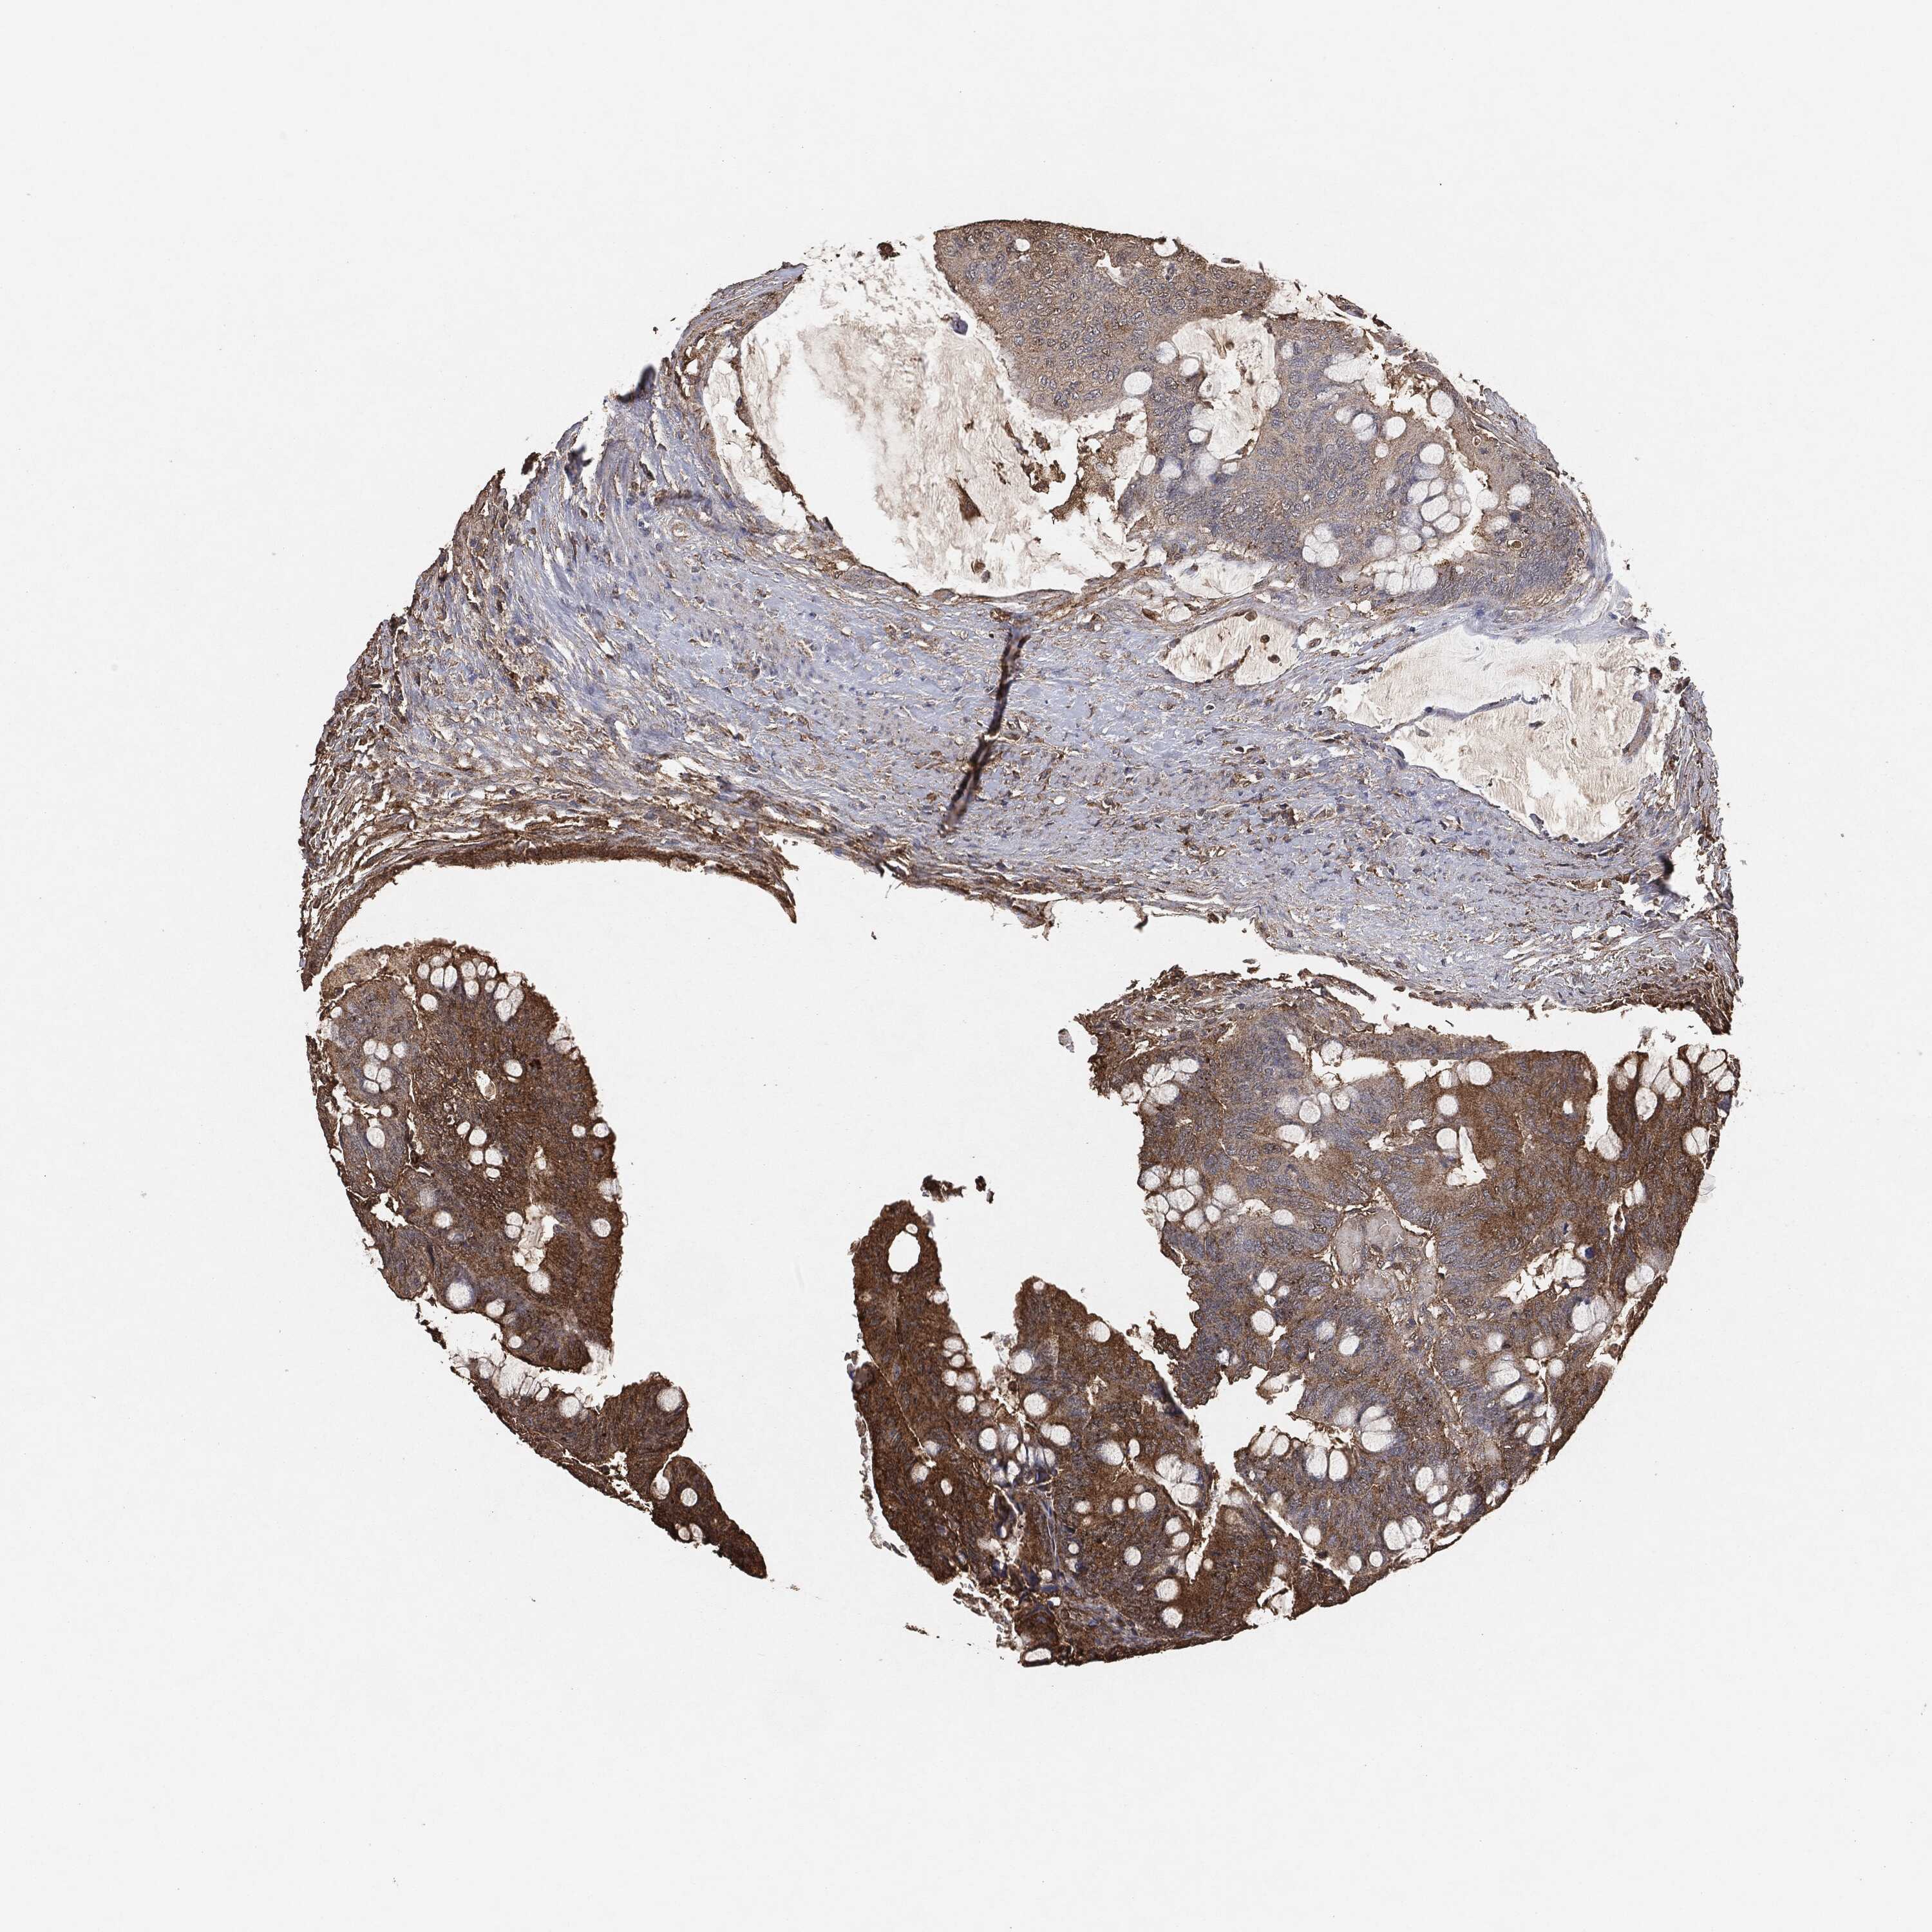

CANCER COLORECTAL CANCER Show tissue menu

Colorectal cancer

Human cancer

Colon adenocarcinoma